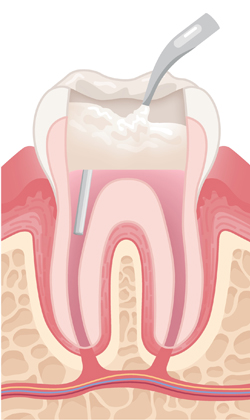

치아 윗부분에 작은 구멍을 만들어 신경관으로 진입할 길을 마련합니다. 이를 통해 내부 염증 부위를 정확히 확인할 수 있습니다.

염증이 생긴 신경과 감염된 조직을 제거하고, 뿌리관 내부를 깨끗하게 청소한 뒤 치료에 적합하도록 넓히고 정돈합니다.

잘 소독된 뿌리관 공간을 영구 재료로 빈틈없이 채워 세균이 다시 침투하지 않도록 봉쇄하는 중요한 단계입니다.

필요 시 치아를 지지할 기둥을 넣고, 접근 통로로 만든 구멍을 충전재로 메워 치아의 구조를 안정적으로 회복시킵니다.

약해진 치아를 보호하기 위해 맞춤 제작된 크라운을 씌워 강도와 기능을 회복시키며, 장기적으로 안전하게 사용하도록 마무리합니다.